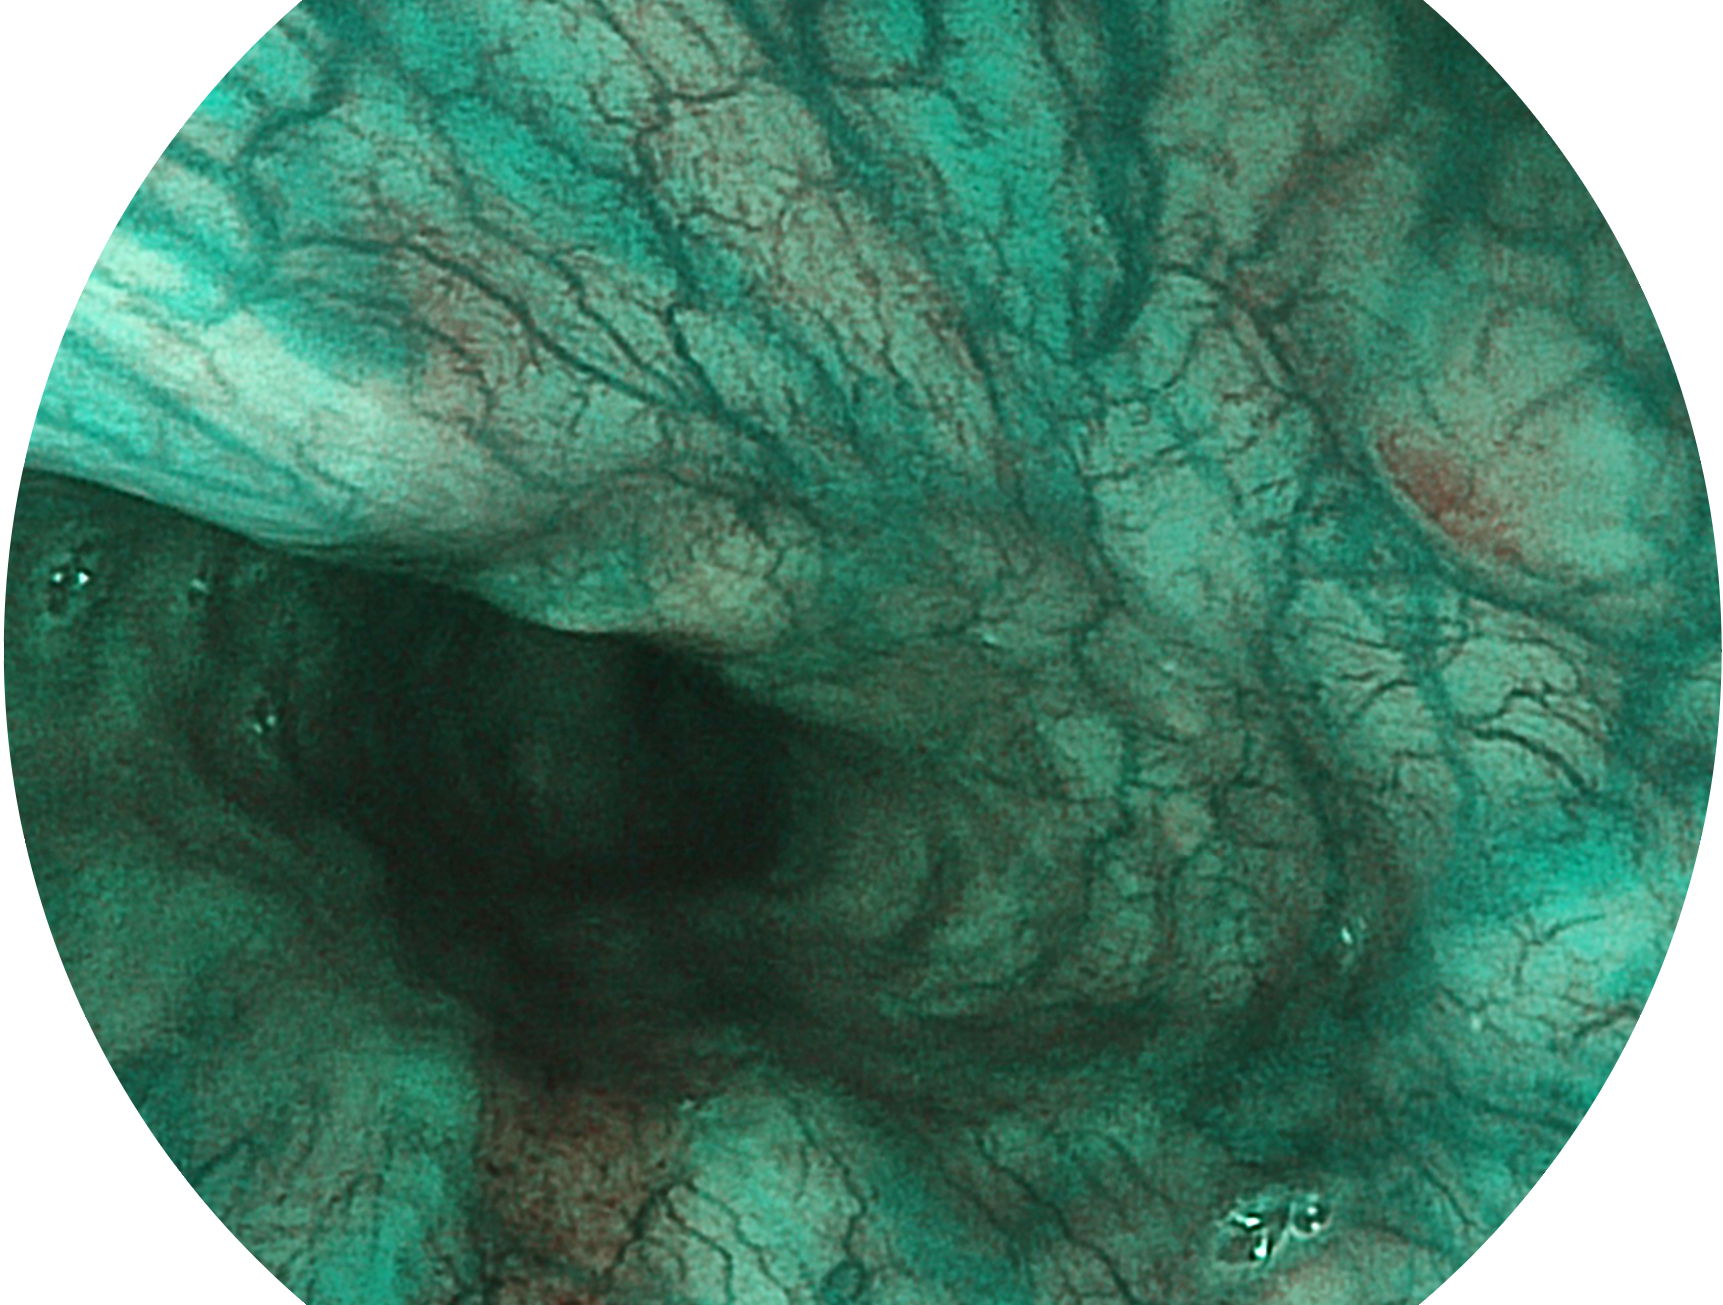

• 白光图像 SFI图像